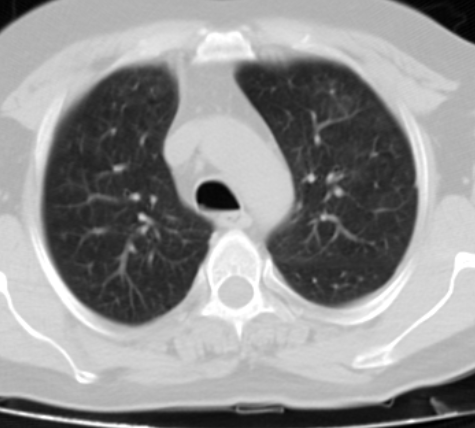

A 40-year-old male patient was admitted to our clinic with complaints of persistent cough for 10 days, phlegm, respiratory distress, fever at intervals, knee pain, and fatigue particularly increased for the past two days. During physical examination, the patient was conscious with poor orientation and cooperation, and was agitated and drowsy. His medical history was able to be obtained from his relatives due to his limited cooperation and orientation. He had a medical history of 20-packyears of smoking and brucellosis 13 years prior. He had a fever of 38.5°C, heart rate was 113 bpm, blood pressure was 100/60 mmHg, and respiration rate was 32/min. Lung auscultation showed bilateral, widespread crepitant rales in all zones of the lungs. Lung sounds were not present in the right basal lung, and dullness was detected with percussion. Cardiovascular examination findings were normal, except for tachycardia. Abdominal examination showed no signs of defense, rebound, or tenderness. Extremities were normal; however, circulatory impairment and cyanosis were present in the periphery. Laboratory test results were as follows: leukocyte 19,900/mm3, hemoglobin 13.7g/dL, hematocrit 40%, platelet count 270,000/mm3, erythrocyte sedimentation rate (ESR) 88mm/hour, and C-reactive protein (CRP) was 15.1 mg/dL. Arterial blood pressure analysis showed that pH was 7.29, PO2 was 76 mmHg, pCO2 was 22mmHg, HCO3 was 11mmol/L, and satO2:94%. Biochemical analysis of blood showed a Na level of 122mmol/L, aspartate aminotransferase (AST) level of 306 IU/mL, and alanine aminotransferase (ALT) of 143.6IU/mL. Metabolic acidosis was present in the arterial blood gas. A posteroanterior radiograph showed bilateral pneumonic infiltration and pleural effusion on the right side (Figure 1). Thoracic computed tomography (CT) showed multiple opacities and right-sided pleural effusion (Figure 2). Serum agglutination titer for Brucella was 1:320. Pleural fluid obtained on thoracentesis was consistent with exudate and hemorrhagic. Pleural fluid tested positive for Rose-Bengal test. Based on clinical and physical examination findings, the patient was diagnosed with brucellosis with lung and pleural involvement. The patient was initiated on ceftriaxone 2 g bid, doxycycline 100 mg bid, and rifampicin 600 mg once daily. His general condition improved on Day 15 of treatment and did not have fever for five days. He was discharged with the recommendation of outpatient follow-up visits. Doxycycline 100 mg bid and rifampicin 600 mg once daily treatment was scheduled to continue until two months (Figures 3 & 4).

Figure 2